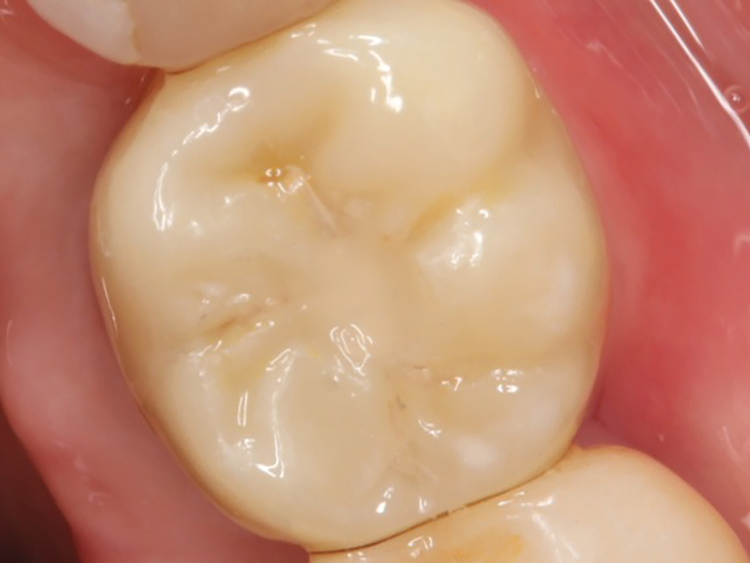

(2.) Preoperative occlusal view of the implant fixture covered by overgrown tissue.

Figure 2

A 61-year-old male patient presented with the chief complaint of a missing implant-supported crown. The patient's dental history revealed a habit of grinding and clenching, and signs of wear were clinically evident during the examination. Because the implant restoration was placed 7 years prior at another practice, and the manufacturer and model were not immediately available, a universal protocol would be required to attempt the rescue. The patient reported that the crown had been dislodged for many weeks. As a result, the soft tissue had grown over the implant, completely covering it (Figure 2). A preoperative periapical radiograph was taken to help visualize the location and size of the remaining fragment (Figure 3). In addition, an intraoral camera would be used during the procedure to view the internal aspect of the fixture and aid in the retrieval process.